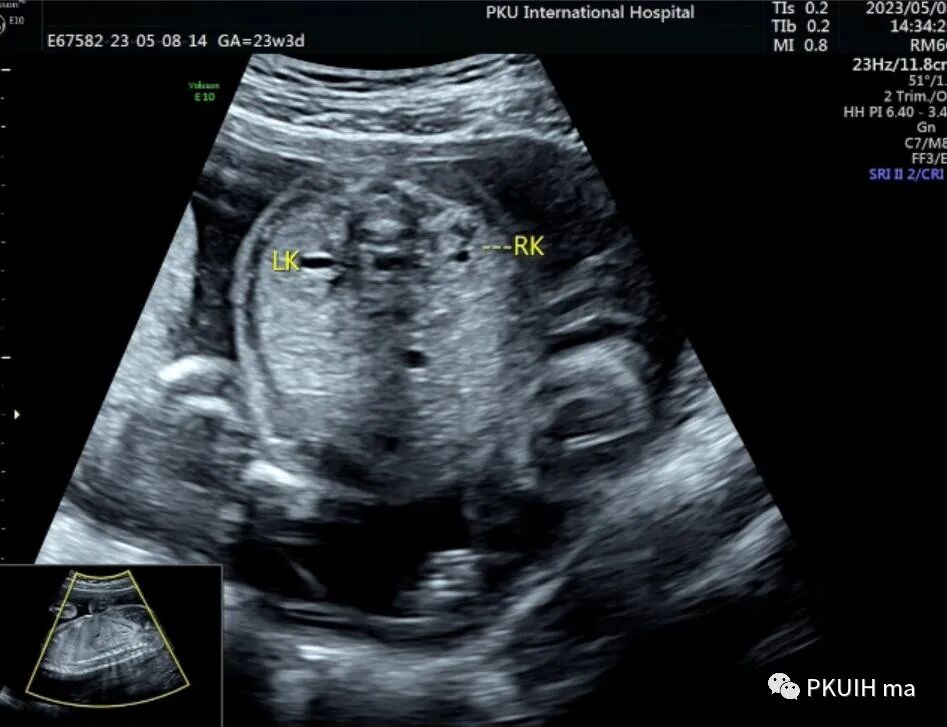

下图分别是23周和27周正常胎儿的肾横断面图像,显示肾门呈水平状,指向内侧,分离的肾盂也呈水平状